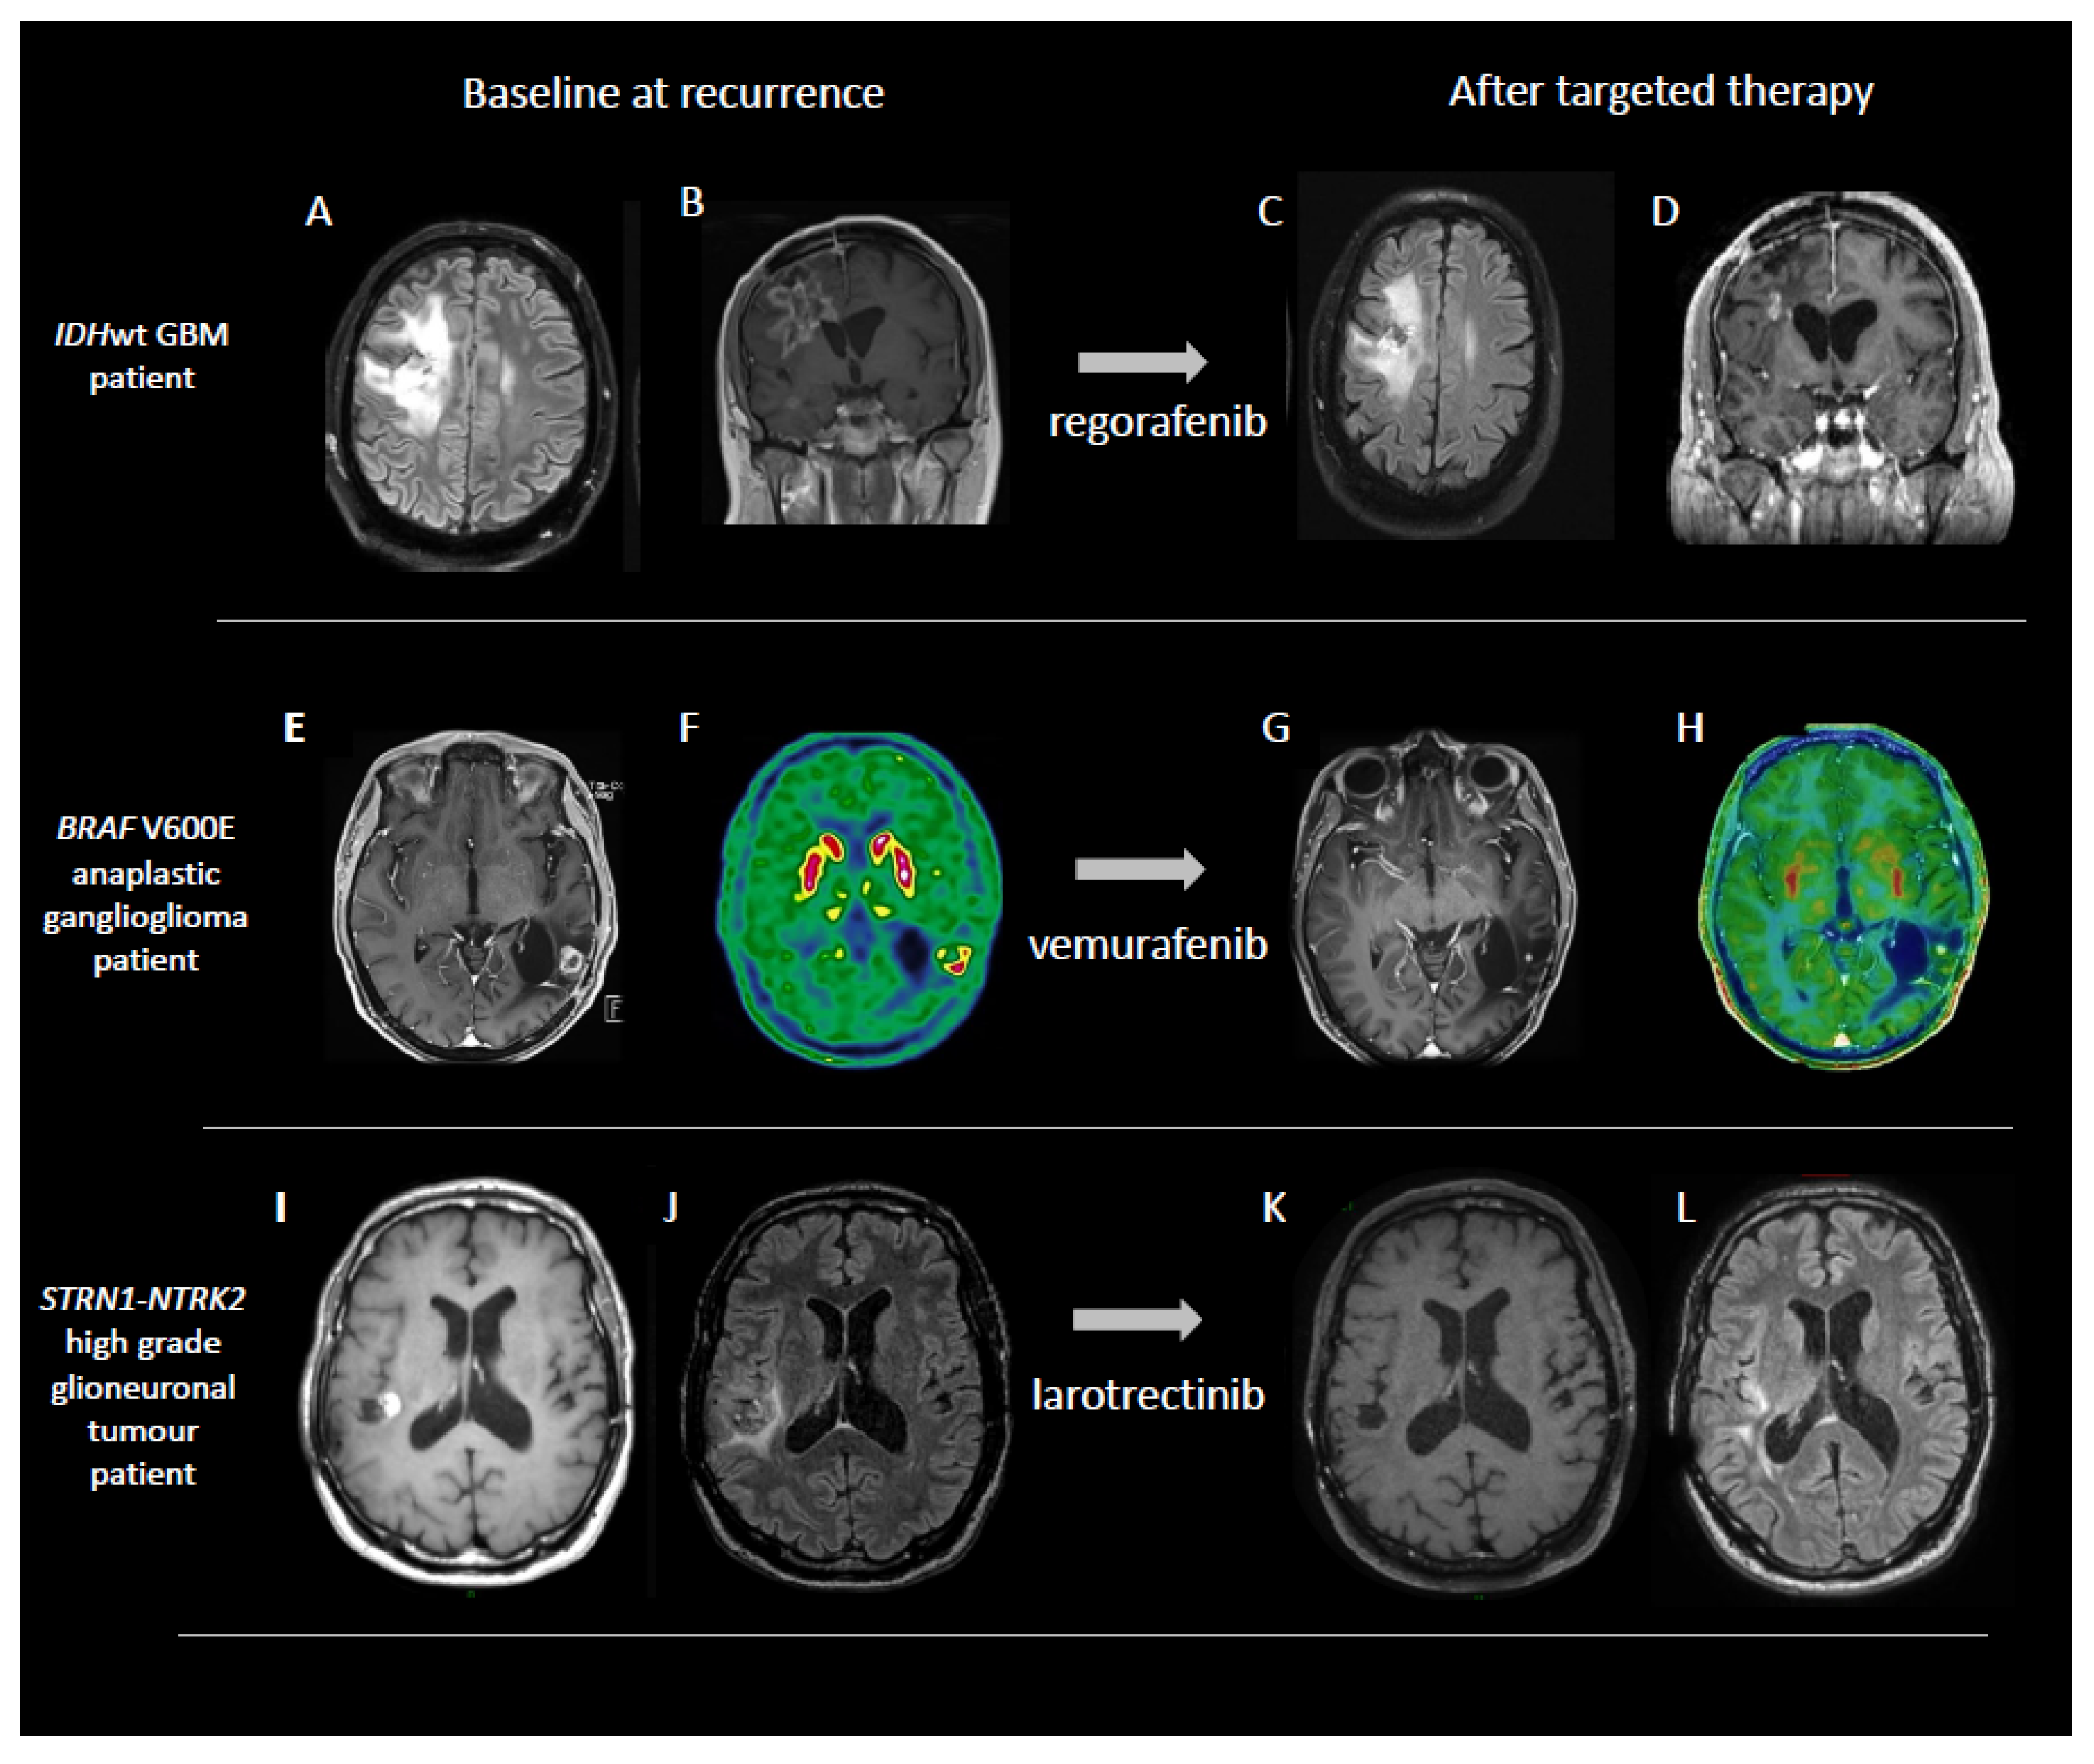

- Berzero, G.; Bellu, L.; Baldini, C.; Ducray, F.; Guyon, D.; Eoli, M.; Silvani, A.; Dehais, C.; Idbaih, A.; Younan, N.; et al. Sustained Tumor Control with MAPK Inhibition in BRAF V600-Mutant Adult Glial and Glioneuronal Tumors. Neurology 2021, 97, e673–e683. [Google Scholar] [CrossRef]

- Boyer, J.; Birzu, C.; Bielle, F.; Goulas, C.; Savatovsky, J.; Karachi, C.; Idbaih, A. Dramatic Response of STRN-NTRK-Fused Malignant Glioneuronal Tumor to Larotrectinib in Adult. Neuro-Oncology 2021, 23, 1200–1202. [Google Scholar] [CrossRef] [PubMed]

5.2. MAP-Kinase Pathway Inhibition

5.3. Inhibition of FGFR3-TACC3 Gene Fusions and Activating Mutations of FGFR1 Gene

5.4. NTRK Pathway Inhibition